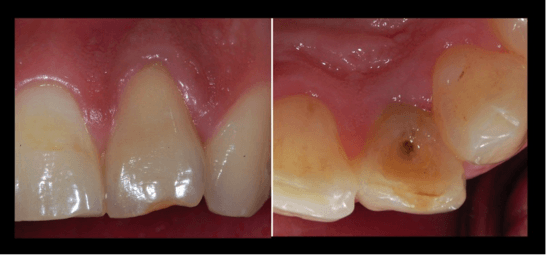

Endodontic Management of an Infected Immature Tooth with Spontaneous Root Closure and Type II Dens Invaginatus

Clinicians frequently encounter the sequlae of trauma, but are rarely present when the trauma actually occurs. It is important to be aware of possible healing responses after dental trauma has occurred.